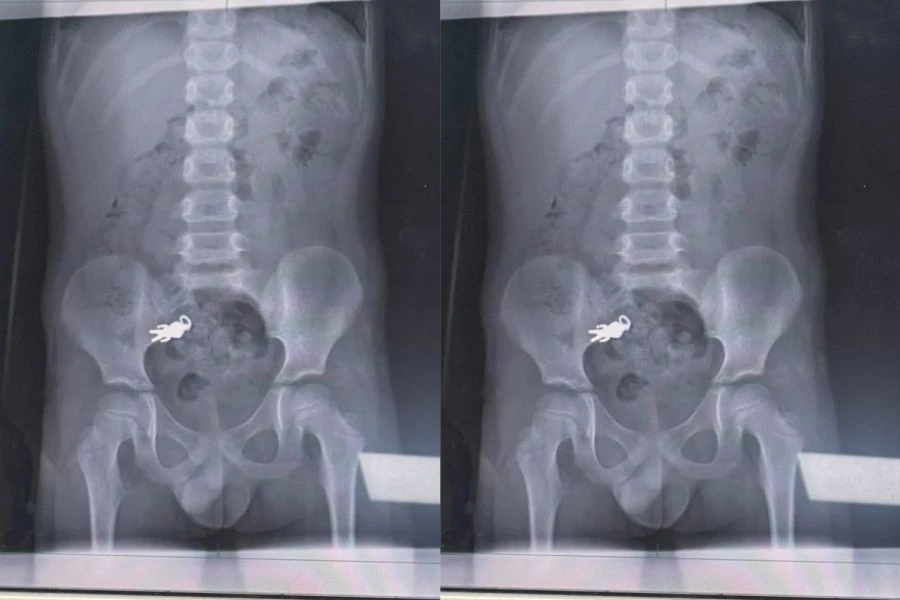

Melalui perkongsian di media sosial, ibu bapa memuat naik gambar X-ray yang menunjukkan rantai kunci berukuran kira-kira 2.8 cm x 1.4 cm berada di dalam usus anak mereka.

Menurut pakar pediatrik, Dr. Hsieh Chintung, rantai kunci tersebut sudah bergerak ke usus kecil dan kanak-kanak itu berada dalam keadaan stabil.